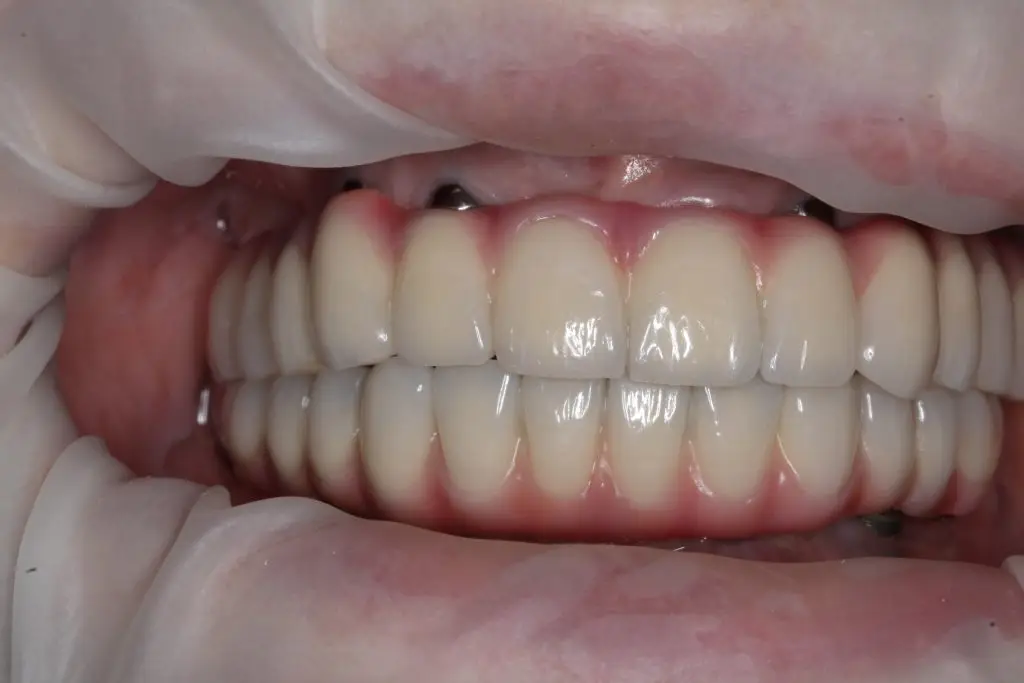

Dupa 6 luni, s-au realizat lucrarile finale pe implanturi, la maxilar si la mandibula.

Pacienta a fost extrem de mulțumită de noul său zâmbet.Zâmbetul i-a redat încrederea și a ajutat-o să se simtă mai bine în interacțiunile sociale și profesionale.

Sistemul All-on-6 este o varianta sigura si predictibila pentru a reabilita cavitatea orala. Acum o pacienta fericita, cu un zâmbet impecabil.